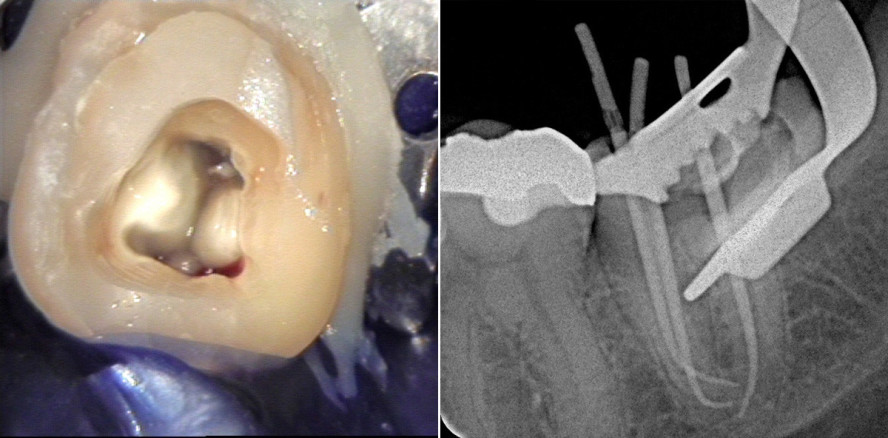

Ein 46-jähriger Patient stellt sich im Oktober 2013 mit pulpitiformen Beschwerden an Zahn 37 vor. Der Zahn ist mit einer Goldteilkrone versorgt, der Randschluss ist unvollständig (Abb. 12). Nach Lokalanästhesie erfolgt die Entfernung der Restauration sowie des Zementaufbaus. Darunter findet sich eine Eröffnung der Pulpakammer (Abb. 13). Die Diagnose lautet Pulpitis aperta. Unter Kofferdam wird zunächst ein adhäsiver, präendodontischer Aufbau aus Komposit erstellt. Gleichzeitig wird bei der Trepanation des Pulpakavums die Kronenpulpa entfernt (Abb. 14). Da es sich um eine Schmerzbehandlung handelt, wird aufgrund der zeitlichen Begrenzung Ledermix als Medikament appliziert und der Zahn adhäsiv mit Komposit verschlossen.

Die Weiterbehandlung im Dezember 2013 erfolgt einzeitig. Nach der Lokalanästhesie wird das Medikament entfernt und der Kanalverlauf mit C+-Feilen der ISO-Größen 06, 08, 10 unter endometrischer Kontrolle sondiert. Die röntgenologische Bestätigung der Arbeitslänge zeigt eine starke, abrupte Krümmung der Kanäle im apikalen Drittel der mesialen Wurzel (Abb. 15). Der Gleitpfad wird mit PathFiles® 013/016/019 (Dentsply Maillefer) präpariert, danach mit im Endo-Bender vorgebogenen ProTaper®-Handfeilen S1 und S2 desselben Herstellers erweitert. Die rotierende Aufbereitung erfolgt mit der HyFlex™ CM.

Im vorliegenden Fall wird in folgender Sequenz mit aufsteigenden Größen und Tapern gearbeitet: 15/.04, 20/.04, 20/.06, 25/.06, 30/.04, 30/.06 sowie 35/.06. Intermittierend wird der Kanalverlauf manuell mit vorgebogenen ProTaper®-Handinstrumenten F1 bis F3 erweitert und anschließend mit den entsprechenden, rotierenden HyFlex™-Feilen perfekt ausgeformt, weil die Instrumente in der mesialen Wurzel aufgrund der extremen Krümmung durch den Drehzahlbegrenzer des Endomotors gestoppt werden. Die gesamte Präparation erfolgt unter intensiver Spülung mit erwärmtem sechsprozentigem Natriumhypochlorit. Darüber hinaus wird eine ultraschallaktivierte Abschlussspülung mit EDTA 17 % und NaOCl für dreimal 20 Sekunden durchgeführt. Nach der Masterpointeinprobe wird der Wurzelkanal mit Guttapercha in modifizierter Schilder-Technik warm-vertikal obturiert (Abb. 16–18). Adhäsiv wird Zahn 37 mit einem Glasfaserstift und Komposit verschlossen (Abb. 19). Die postoperative Röntgenkontrolle nach einem Jahr bzw. circa 4,5 Jahren zeigt dauerhaft reizlose apikale Verhältnisse (Abb. 20 und 21).